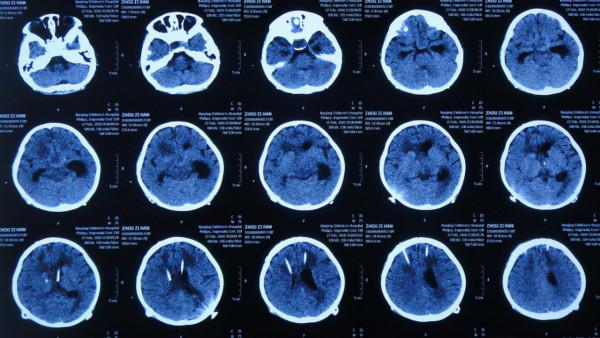

第2家醫院繼續治療8天時間內,期間4次查頭部CT示腦室逐漸再次擴張(圖-10、圖-11、圖-12、圖-13)。

圖-10:2019年12月18日頭部CT

圖-11:2019年12月19日頭部CT

圖-12:2019年12月22日頭部CT

圖-13:2019年12月25日頭部CT